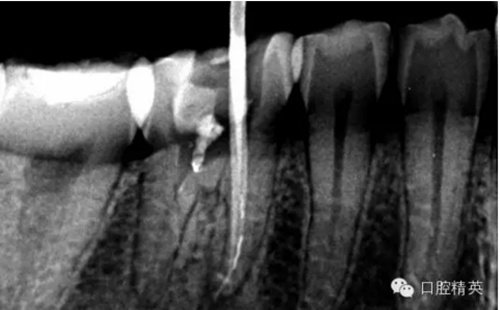

近舌8號(hào)k挫疏通,根尖部彎曲,我花費(fèi)時(shí)間2小時(shí)疏通。我個(gè)人覺(jué)得根管能否被疏通,第一個(gè)重要因素是時(shí)間,因?yàn)樽鳛檠荔w牙髓的醫(yī)生,首先就是需要的就是耐心。我個(gè)人覺(jué)得耐心是非常重要,因?yàn)楹芏喔鼙皇柰〞r(shí),都是我們快要放棄的時(shí)候。所以我每次都會(huì)安慰自己快好了,快好了,就差一點(diǎn)點(diǎn),在堅(jiān)持一會(huì)兒就好了。可以說(shuō)沒(méi)有耐心,想做好牙體牙髓,我個(gè)人覺(jué)得很難很難。第二個(gè)就是手法,不知道大家啟用挫是什么挫,一般我個(gè)人認(rèn)為,最好從8號(hào)開(kāi)始疏通,這樣不容易在狹窄的根管內(nèi)形成臺(tái)階(如果有條件的可以從6號(hào)開(kāi)始)。

這個(gè)病例難以疏通在于根中上段堵塞,根尖下段有臺(tái)階的形成,感覺(jué)不到彎曲的方向。首先我們處理根上段,我們可以采取的方法是先預(yù)備跟中上段,將它擴(kuò)開(kāi)來(lái),這樣有利于根尖下段的預(yù)備,建立良好的視野。對(duì)于根尖下段的臺(tái)階和彎曲 ,8號(hào)挫預(yù)彎,第二步要知道根管彎曲的方向,沿著根管彎曲的方向疏通。特別是有臺(tái)階的地方,一定不要硬來(lái),慢慢旋轉(zhuǎn)找到根管彎曲的方向(結(jié)合x(chóng)線片)避開(kāi)臺(tái)階,一定要記住慢慢旋轉(zhuǎn)角度越小越好,正旋逆旋找“緊點(diǎn)”,有經(jīng)驗(yàn)的醫(yī)生大概都知道,找到了“緊點(diǎn)”就等于找到了希望。手法一定要輕柔不易暴力!切記切記!戒浮戒躁(這句話也是特別要告訴我自己)。